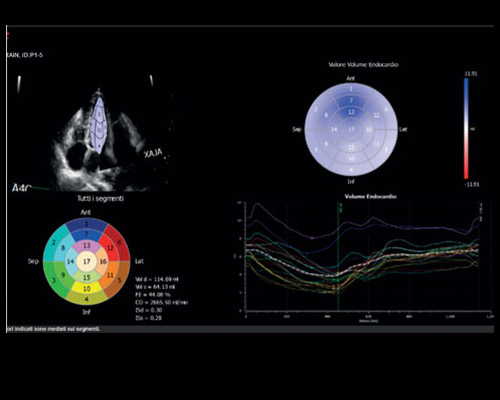

Research and successfully implement the limitless ultrasound technologies such as MicroE – Detect microcalcification; Xstrain4D – Cardiac strain 4D; XSTIC – Spatial-Temporal Image Correlation

MyLab X8 eXP integrates latest technologies, delivering high level of image quality with optimal workflow, efficiency